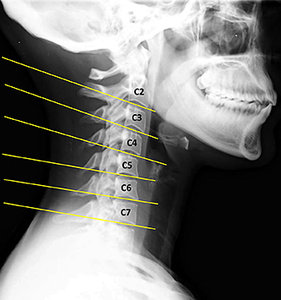

FIG 1 Lateral cervical view of text neck.

Reproduced with permission from Healthyspines.org.

When history and physical findings warrant, cervical X-ray examination may also be part of the assessment. The lateral cervical view in Fig. 1 illustrates some of the findings we would anticipate with chronic text neck. There is evident loss of cervical curve indicated by "military neck or reversed cervical curve." Disc plane lines do not converge to the posterior, but remain parallel or even diverge. Fig. 1 also demonstrates flexion malposition of C4 on C5 (open posterior disc wedge).